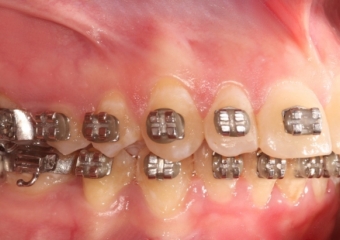

Mordida inicial